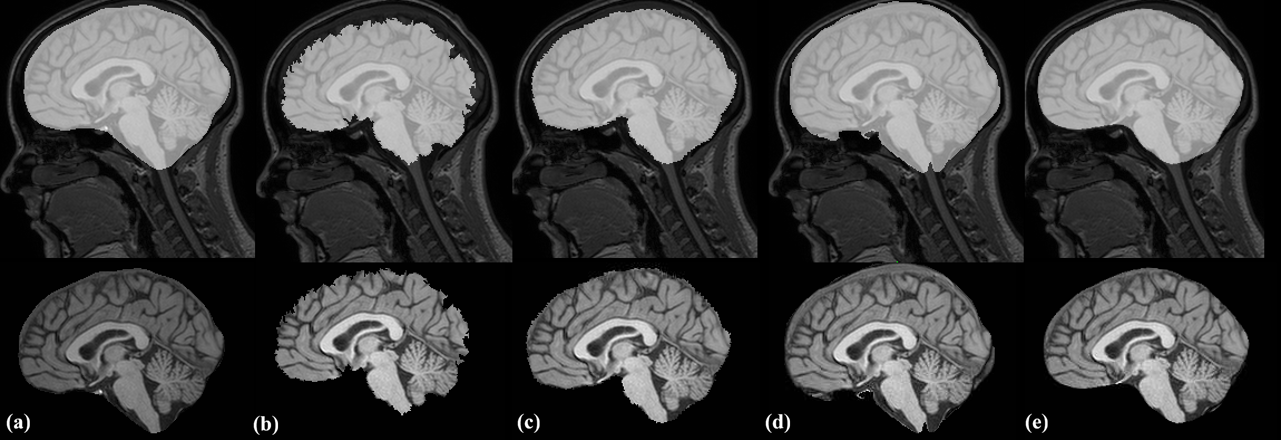

For qualitative analysis, we performed a visual inspection of results from all methods. Our analysis shows that the proposed method is highly consistent in the amount of CSF included in the segmentations. The method also demonstrates high robustness towards pathologies and movement artefacts, as demonstrated in Figure 2, where MONSTR and Synthstrip (without CSF) remove a significant amount of brain tissue, while the proposed method better preserves brain tissue. In some cases, MONSTR removed a large amount of tissue in the brainstem, which is often critical to subsequent analysis, while our model correctly preserved it. Figure 3 shows an example from the held-out test set, showcasing Synthstrip’s oversegmentation, where it occasionally includes the meninges around the brain tissue. This inconsistent inclusion of the meninges can be problematic for subsequent image processing. An example from the external indepdendent test set can be seen in Figure 4.

![]() |